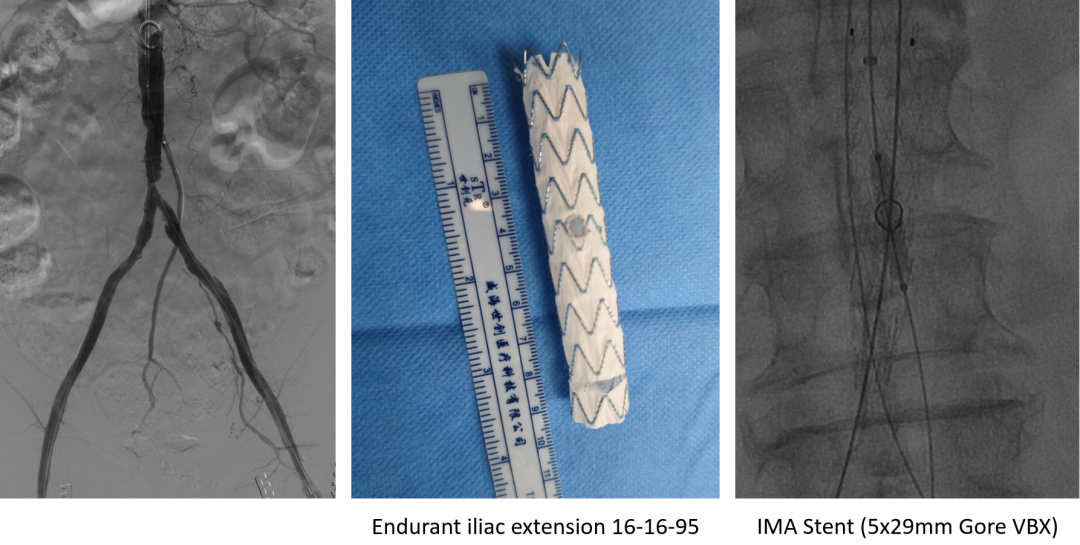

左侧肱动脉入路,主髂动脉造影

双侧股动脉切开,经股动脉7F Fogarty导管取栓